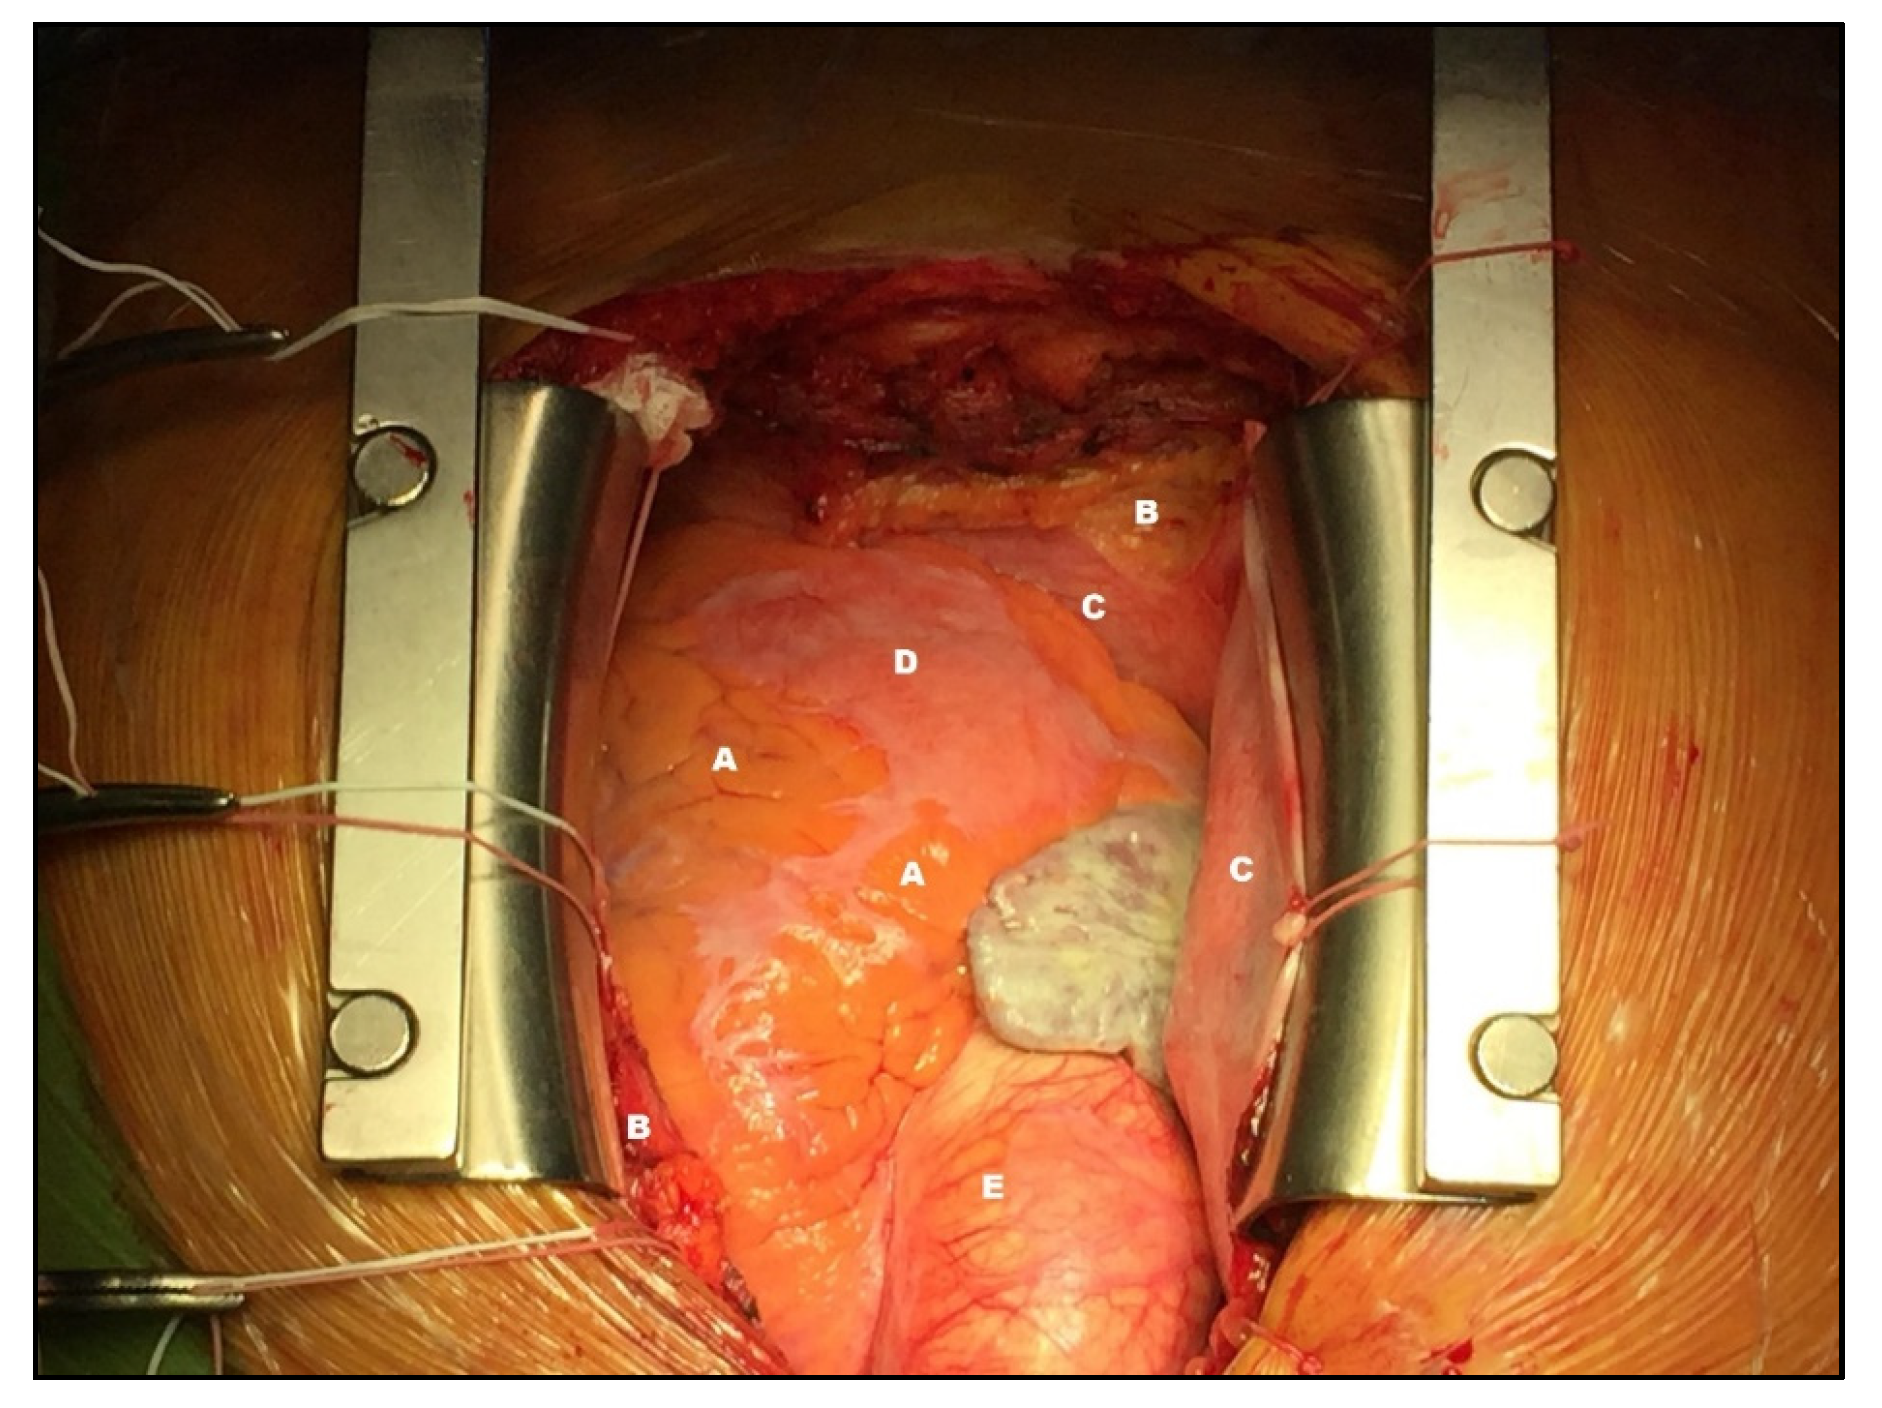

2. Anatomy